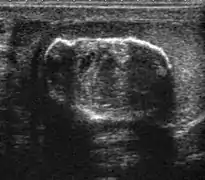

Sonography of a normal testis. The normal testis presents as a structure having homogeneous, medium level, granular echotexture. The mediastinum testis appears as the hyperechoic region located at the periphery of the testis as seen in this figure.

The normal adult testis is an ovoid structure measuring 3 cm in anterior-posterior dimension, 2–4 cm in width, and 3–5 cm in length. The weight of each testis normally ranges from 12.5 to 19 g. Both the sizes and weights of the testes normally decrease with age. At ultrasound, the normal testis has a homogeneous, medium-level, granular echotexture. The testicle is surrounded by a dense white fibrous capsule, the tunica albuginea, which is often not visualized in the absence of intrascrotal fluid. However, the tunica is often seen as an echogenic structure where it invaginates into the testis to form the mediastinum testis. In the testis, the seminiferous tubules converge to form the rete testes, which is located in the mediastinum testis. The rete testis connects to the epididymal head via the efferent ductules. The epididymis is located posterolateral to the testis and measures 6–7 cm in length. At sonography, the epididymis is normally iso- or slightly hyperechoic to the normal testis and its echo texture may be coarser. The head is the largest and most easily identified portion of the epididymis. It is located superior-lateral to the upper pole of the testicle and is often seen on paramedian views of the testis. The normal epididymal body and tail are smaller and more variable in position.